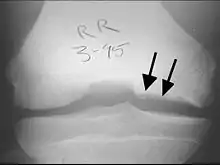

TOC generalmente causa dolor e hinchazón de la articulación afectada y bloqueos de la circulación. El examen físico revela un derrame, sensibilidad y crepitación. El TOC puede ser difícil de diagnosticar porque los síntomas parecen a otras enfermedades. Sin embargo, la enfermedad puede ser confirmado por los rayos X, la tomografía computarizada (CT) o imágenes de resonancia magnética (MRI) explora. OCD está clasificada por estas técnicas de imagen, o por artroscopia de la articulación, y representada en las fases (I, II, III y IV), de la progresión de la enfermedad. Tras el diagnóstico de la enfermedad puede ser tratado, dependiendo de su gravedad, por la reparación del cartílago.[5][6] El tratamiento no quirúrgico rara vez es una opción, ya que el cartílago tiene una limitada capacidad para curar. Como resultado, incluso moderados casos requieren algún tipo de cirugía. Cuando sea posible, no el tipo de gestión como protegidas peso (parcial o no del peso) y la inmovilización se utilizan. El tratamiento quirúrgico varía ampliamente e incluye la perforación de lesiones artroscópicas intactas, la seguridad de las lesiones del cartílago solapa con clavijas o tornillos, la perforación y la sustitución de cartílago enchufes, trasplante de células madre, y reemplazo de articulaciones.

En osteocondritis disecante, fragmentos de cartílago o de hueso se aflojan dentro de una articulación, provocando dolor e inflamación. Estos fragmentos se refieren a veces como los signos comunes.[8] El TOC es un tipo de osteocondrosis en el que una lesión se ha formado en la capa de cartílago en sí, dando lugar a la inflamación secundaria. TOC afecta más comúnmente a la rodilla, aunque puede afectar otras articulaciones como el tobillo o el codo.

La exploración física suele revelar un derrame, la ternura, y crepitación. El dolor puede extenderse al principio, pero a menudo vuelve a un conjunto bien definido como el punto focal de la lesión progresa. Así como las cuotas de los síntomas del TOC con enfermedades comunes, fractura osteocondral aguda tiene una presentación similar con ternura en la articulación afectada, pero generalmente se asocia con una hemartrosis grasos. Aunque no hay marcha patológica significativa o anomalía alineación característica asociada con este trastorno, el paciente puede caminar con la pierna afectada en rotación externa en un intento de evitar la interacción de la espina tibial en la cara lateral del cóndilo interno del fémur.[11]